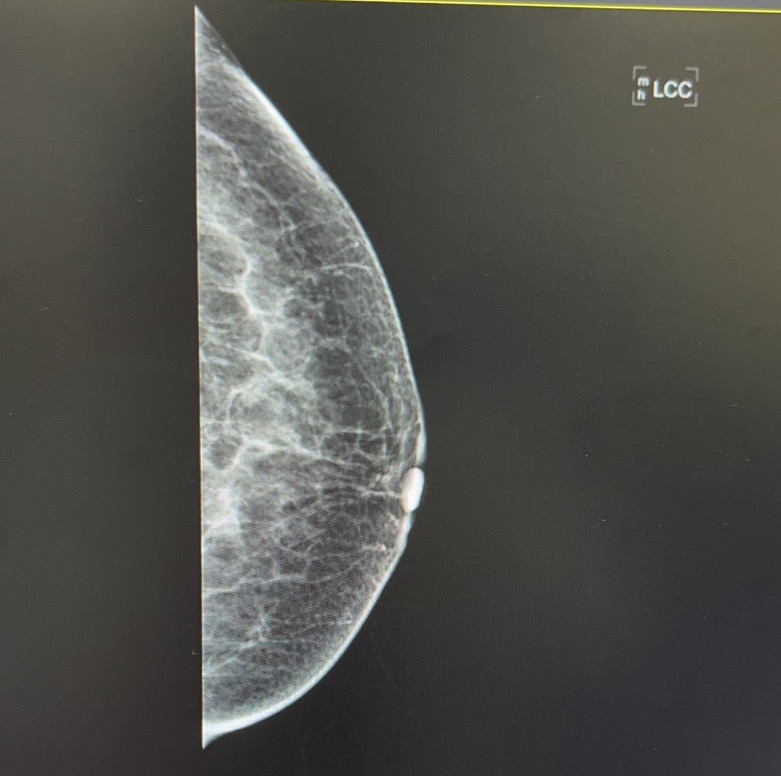

2023-05-14 日常动态 #x线下的艺术 1 评论 1 喜欢 分享 凹凸的世界 在这里带上了面具?,也是摘下了面具。 查看TA的全部内容 +关注 红楼go 去发现更多有趣内容 微信扫码打开红楼go小程序 体验更多「红楼go」新功能 评论 1 糖糖 2023-05-14 0 惊艳 我也来讲两句